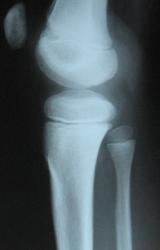

Мальчик 10 лет. Травма 1 год назал ( сомнительная).  4 мес. назад обнаружили плотное образование в обл. бугристости бб. кости. За это время увеличелось на 13. При пальпации очень плотное, без болезненное, не подвижное. Ваше мнение? Нужна ли активная хирургическая тактика?

С учётом клиники, можно предположить, что речь идёт болезни Осгуд-Шляттера, хотя привычной картины для этой болезни не видно на снимке. А, что за метод представлен на 3 слева снимке?

Я однажды наблюдала рост костно-хрящевого экзостоза из бугристости большеберцовой кости. Возможно, здесь тоже самое.

А что за участок разрежения в метафизе бедра?

Согласен с коллегой. Весьма "интересный" участок в области дистального метафиза бедренной кости.

Если на на снимке не визуализируется,  но при этом образование как вы пишите плотное и имеет место быть атрофии кортикала от давления, можно предположить о хондроме.

А ведь "тенюху" то видно она на широком основании,  ещё возможно хрящевой экзостоз.

Возможно, на структурном снимке и будет видна тень. Хорошо видна нечеткость контура кортикального слоя по переднему контуру б/берцовой кости в области проксимального метафиза.